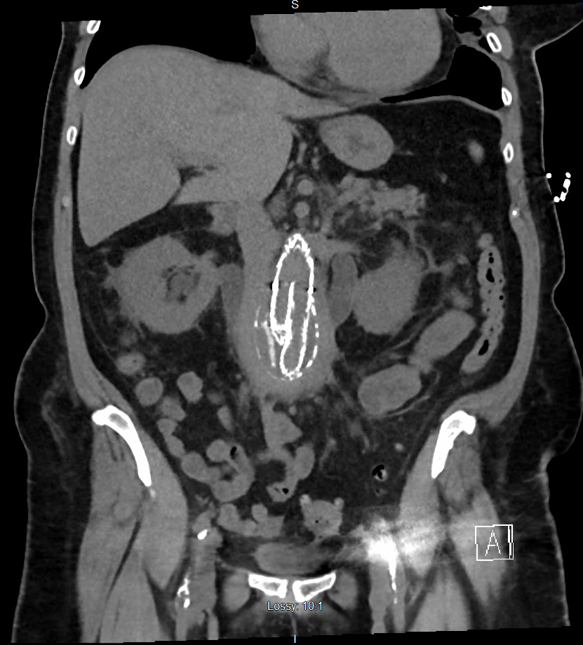

Case Presentation: Case 1: A 66 year old female presented in October 2017 with generalized weakness, fatigue, abdominal pain, and oliguria. The symptoms have been worsening since her abdominal endovascular aneurysm repair (EVAR). She had her EVAR done in August 2017. In the Emergency Room the patient was afebrile with a temperature of 36.4 C, pulse of 76 bpm, respiratory rate of 19, and blood pressure of 193/105. Laboratory studies showed a BUN of 98mg/dL, Creatinine of 17.93mg/dL, Sodium of 128mmol/L, Potassium of 6.1mmol/L, and Anion Gap of 18. A CT chest/abdomen/pelvis was done, and showed moderate bilateral hydroureteronephrosis, increased soft tissue thickening surrounding aneurysm sac suggestive of inflammatory/fibrotic changes and ureteral obstruction. A C-Reactive Protein level of 21.60mg/dL and a Erythrocyte Sedimentation Rate of 96mm/hr were found. She was admitted to the ICU and a Nephrology and Urology consult were placed. Bilateral ureteral stents were placed and the patient started to improve.